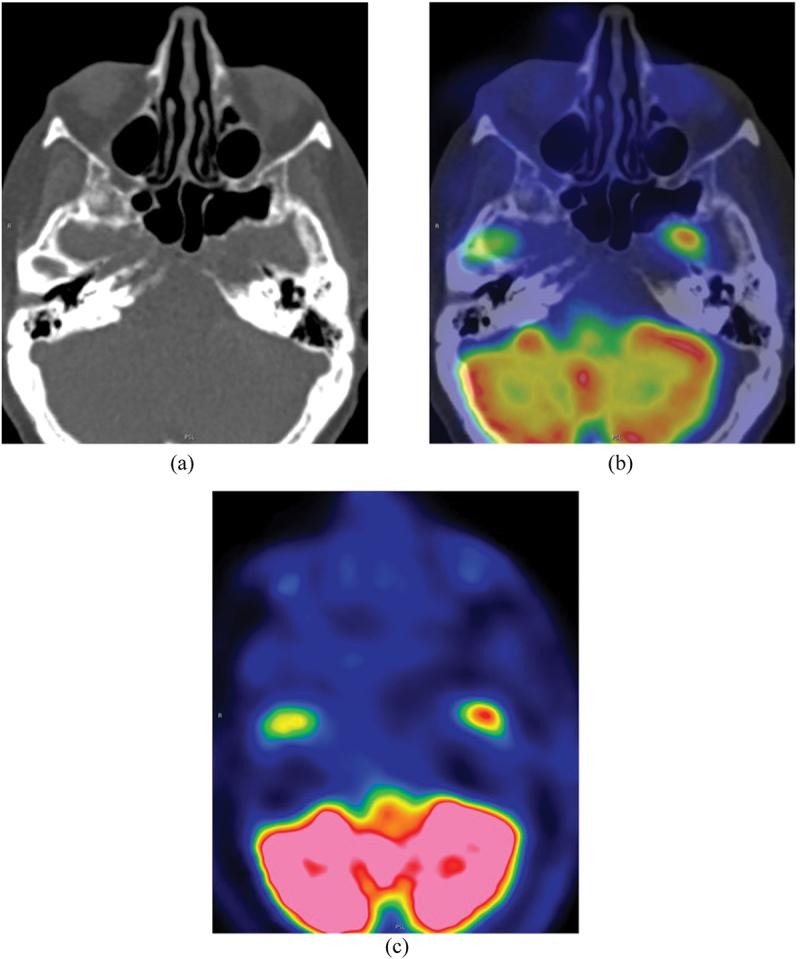

Methotrexate is a commonly employed folate antagonist used as a disease modifying antirheumatic drug. It is recommended by the European League Against Rheumatism Guidelines as an add-on therapy for the treatment of polymyalgia rheumatica. Lymphoproliferative disease developing during methotrexate treatment is recognised as methotrexate-associated lymphoproliferative disorder. We describe a patient with polymyalgia rheumatica on long-term methotrexate treatment presenting with double vision and systemic symptoms concerning for giant cell arteritis. Two months prior, she had noticed a mass of the right nasal dorsum. Neuroimaging showed several lesions of the nasal cavity and a clival lesion. Nasal cavity biopsy revealed diffuse large B-cell lymphoma, and FDG-PET/CT 3 weeks after methotrexate cessation showed significant interval disease regression, confirming the diagnosis of methotrexate-associated lymphoproliferative disorder. Follow-up FDG-PET/CT 4 months after methotrexate cessation showed complete radiological regression of lymphoproliferative lesions. The cumulative incidence of methotrexate-associated lymphoproliferative disorder in patients with rheumatoid arthritis treated with methotrexate has been reported to be up to 4.7% at 10 years in a retrospective study. Cessation of methotrexate resulted in spontaneous regression in 59% of patients. It is important to include methotrexate-associated lymphoproliferative disorder on the differential diagnosis for patients on long-term methotrexate treatment who present with neuro-ophthalmic symptoms and signs as tissue diagnosis prior to commencing steroid treatment is essential to secure the diagnosis and guide treatment.

甲氨蝶呤是一种常用的叶酸拮抗剂,用作改善病情抗风湿药。欧洲抗风湿病联盟指南推荐其作为治疗巨细胞动脉炎的附加疗法。在甲氨蝶呤治疗期间发生的淋巴增殖性疾病被认为是甲氨蝶呤相关淋巴增殖性疾病。我们描述了一名长期接受甲氨蝶呤治疗的巨细胞动脉炎患者,出现复视和全身症状。两个月前,她注意到右鼻背有一个肿块。神经影像学检查显示鼻腔有多处病变以及一个斜坡病变。鼻腔活检显示为弥漫性大B细胞淋巴瘤,停用甲氨蝶呤3周后的FDG-PET/CT显示病情有显著的间隔期消退,证实了甲氨蝶呤相关淋巴增殖性疾病的诊断。停用甲氨蝶呤4个月后的随访FDG-PET/CT显示淋巴增殖性病变完全影像学消退。一项回顾性研究报告称,接受甲氨蝶呤治疗的类风湿关节炎患者中甲氨蝶呤相关淋巴增殖性疾病的累积发病率在10年时高达4.7%。停用甲氨蝶呤后,59%的患者病情自发缓解。对于长期接受甲氨蝶呤治疗且出现神经眼科症状和体征的患者,在鉴别诊断中纳入甲氨蝶呤相关淋巴增殖性疾病很重要;因为在开始使用类固醇治疗之前进行组织诊断对于确诊和指导治疗至关重要。